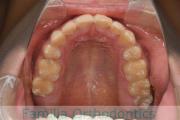

- ≫治療後

上下とも前歯の叢生(でこぼこ、凹凸、ガタガタ)がありましたので、保定をしっかりやらないと後戻りのリスクが出てきます。

上顎

下顎

前歯の関係など

右側

正面

左側